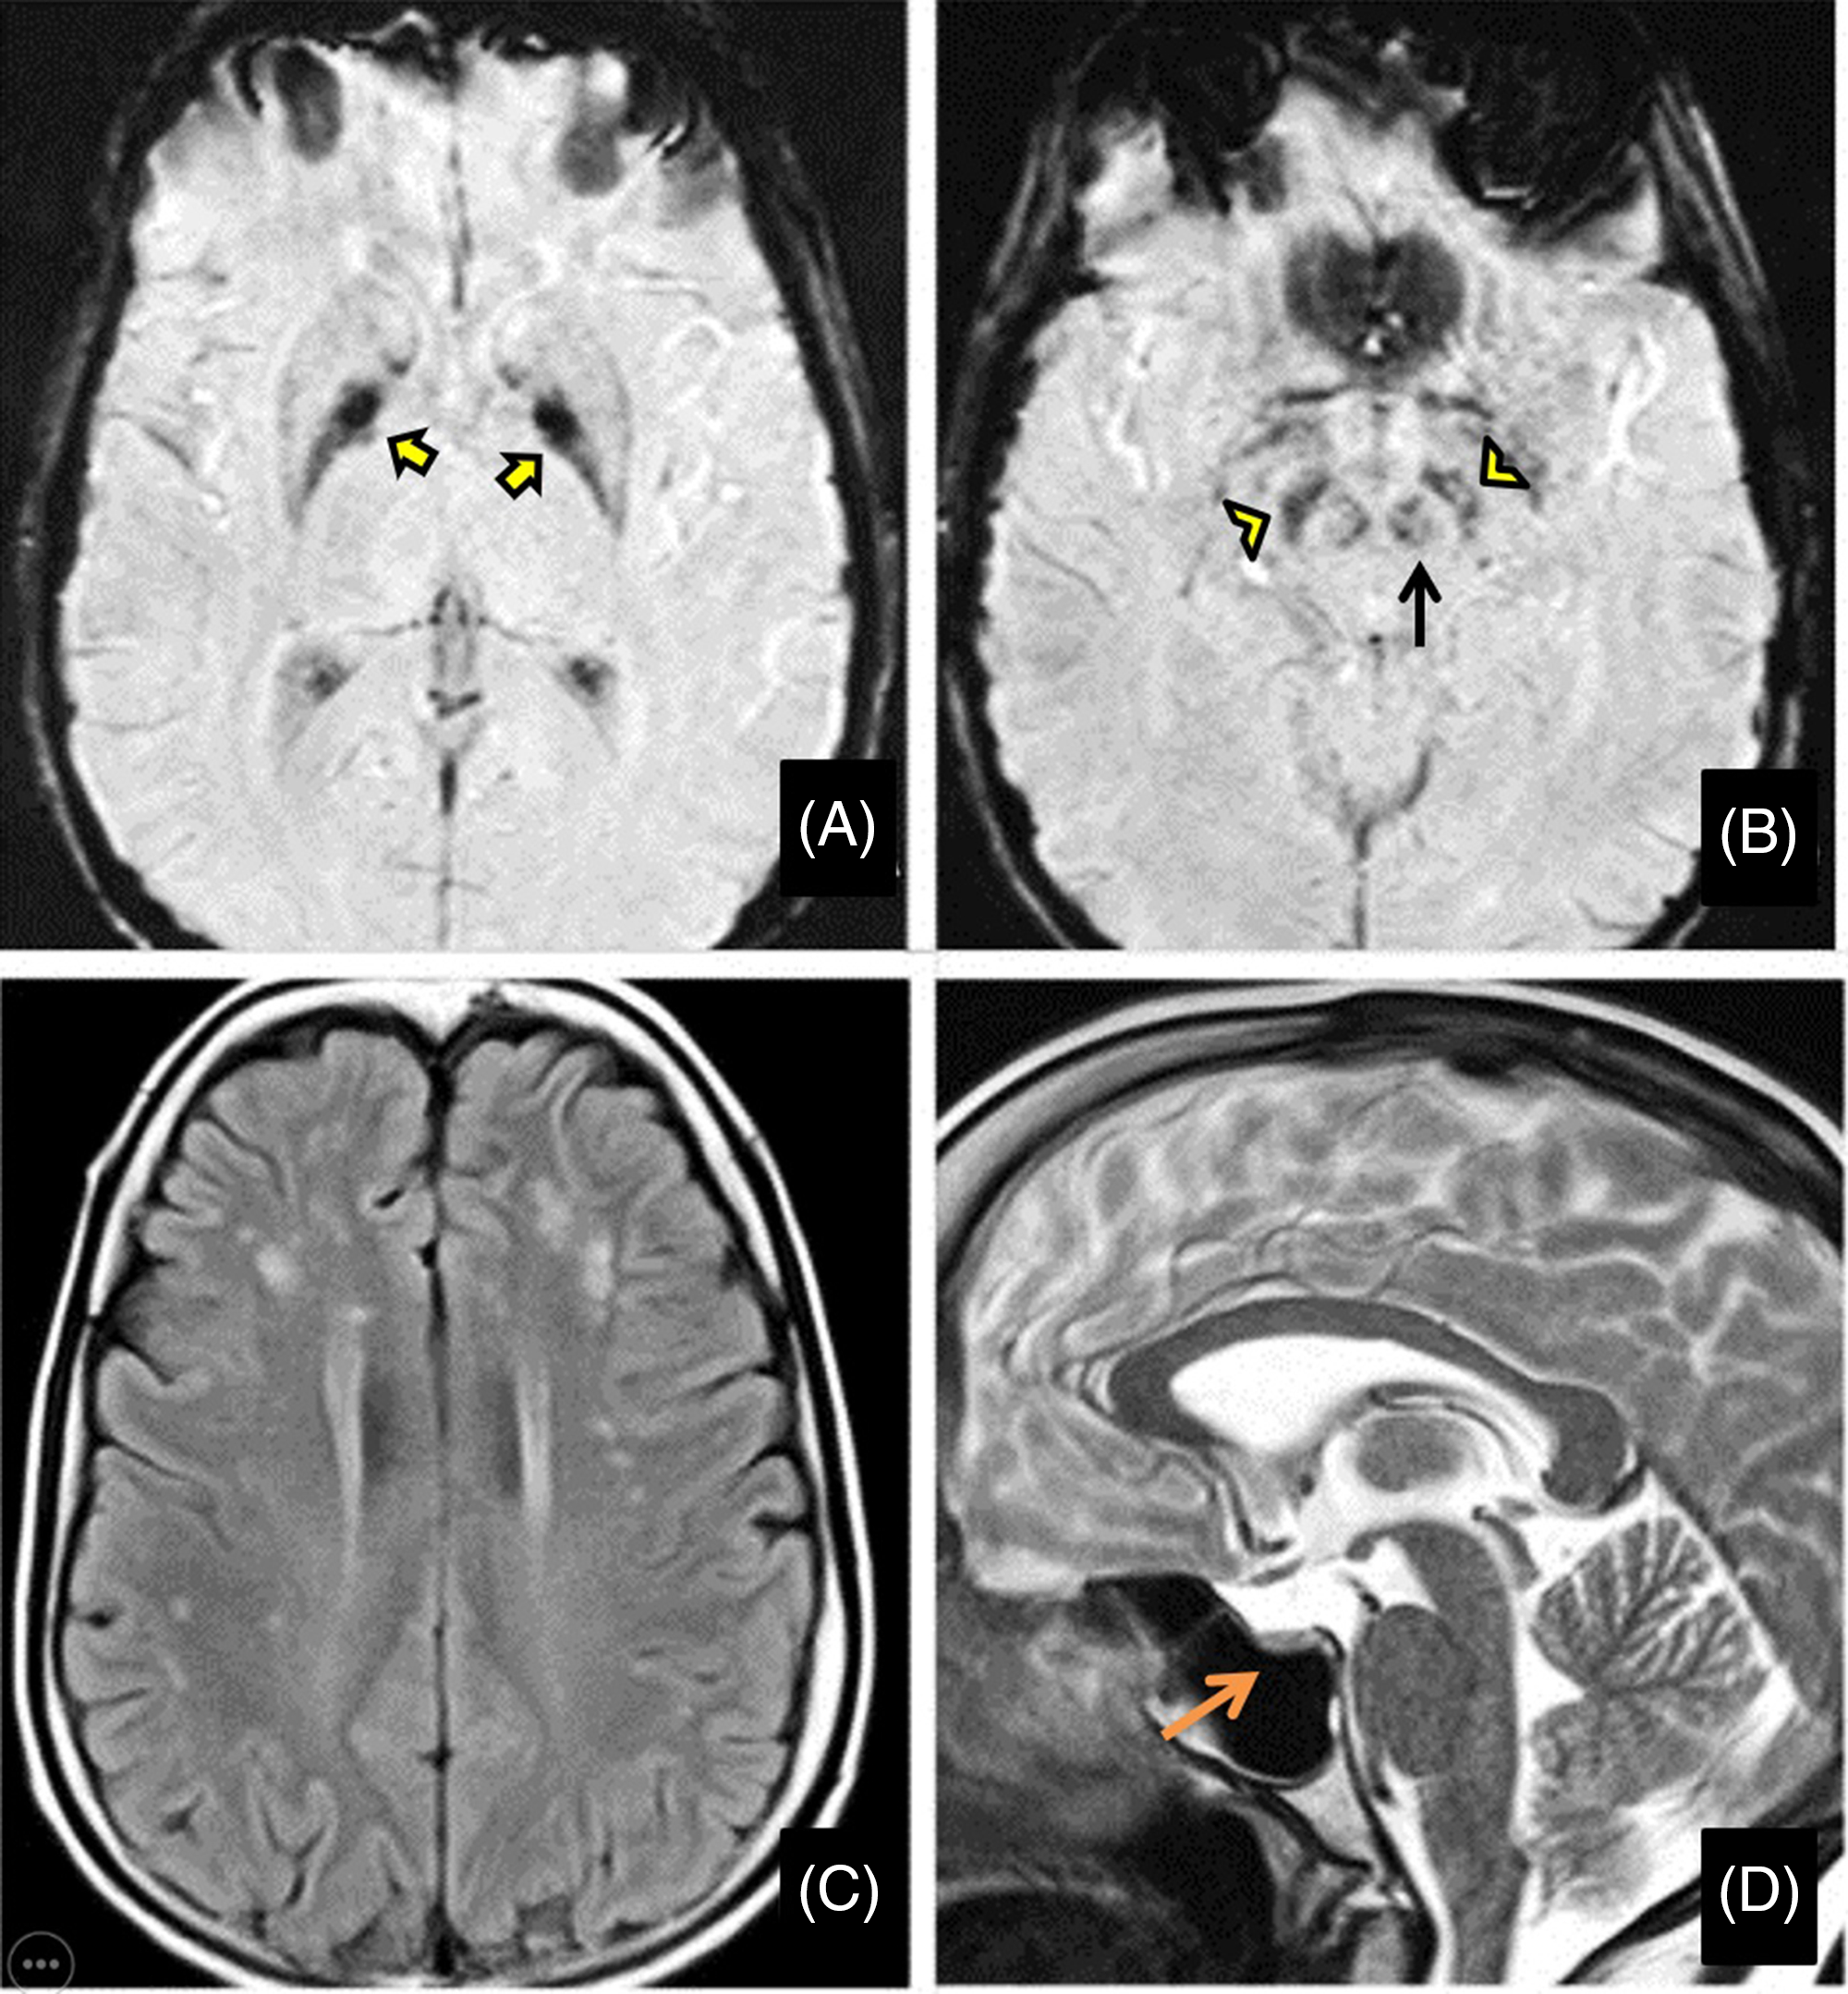

Her routine blood investigations were normal except for hyperglycemia. Electrocardiogram and echocardiography were within normal limits. Pure tone audiometry showed bilateral mild sensorineural hearing loss. Magnetic resonance imaging (MRI) brain showed mineralization in bilateral globus pallidus interna, substantia nigra, and red nucleus on susceptibility-weighted images (SWI) (Figure 1A and B) along with bilateral frontoparietal discrete white matter hyperintensities on T2-weighted images(Figure 1C) and partial empty sella with small-sized hypophysis (Figure 1D). Serum estradiol level of 23.2 pg/mL (normal range in premenopausal females being 30–400 pg/mL) and progesterone levels of 0.04 ng/mL (normal range being 0.1–0.7 ng/mL in the follicular stage and 2–25 ng/mL in the luteal stage) were low, whereas serum follicular stimulating hormone (FSH) level of 33 IU/L(normal range 3–10 ), luteinizing hormone (LH) level of 27.4 IU/L (normal range 2–8 ) were high suggesting a hypergonadotropic hypogonadism secondary to ovarian failure. Ultrasound pelvis showed a small infantile uterus with ill-defined ovaries.

Figure 1: Magnetic resonance imaging (MRI) of the brain shows mineralization in bilateral globus pallidus interna (yellow arrows), substantia nigra (yellow arrowheads), and red nucleus (black arrow) on susceptibility-weighted images (A and B) along with bilateral frontoparietal white matter hyperintensities on T2-weighted images (C) and partial empty sella with small sized hypophysis (D-orange arrow).